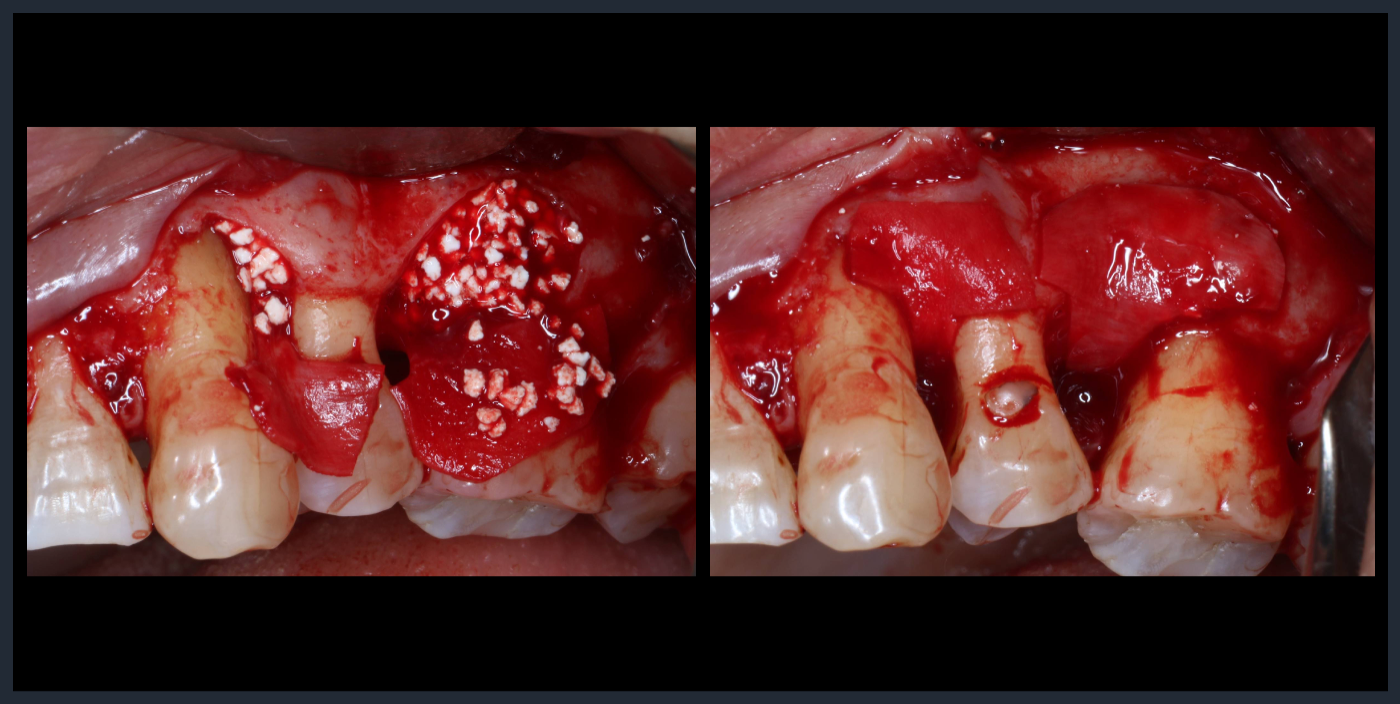

歯周組織再生療法

Periodontal tissue regeneration therapy

Periodontal tissue regeneration therapy

サイトランス+Bio-Gide、血餅を作り、スペースを維持するために、骨補填材+メンブレンを設置した。